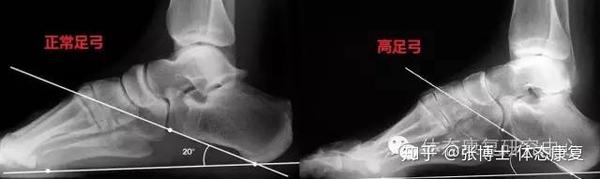

你的足弓正常吗 高足弓形成机制与危害 知乎

尔康百旺医院 什么是高弓足 爪形足 畸形